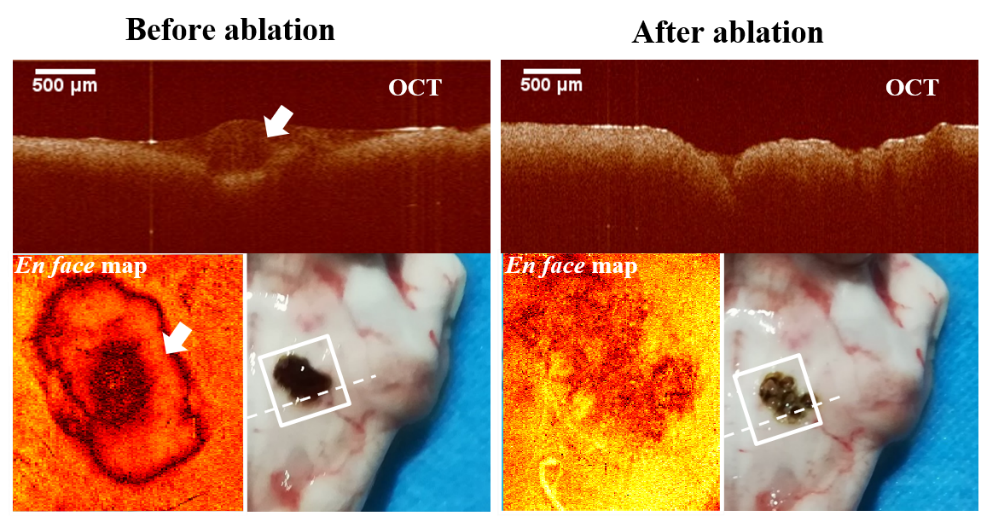

基于非共光路的OCT图像引导自动化激光消融诊疗系统

OCT引导激光消融前后肿瘤区域(白色箭头指向肿瘤)